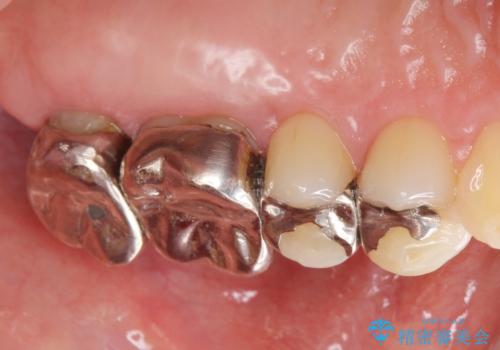

- 銀歯をやりかえたいが他院で抜歯と言われセカンドオピニオンで来院。適合の悪い被せ物が入っており、まずは古い材料、虫歯をとり保存可能か確かめる必要があり、拡大鏡下で全て取り除いたら歯質が歯茎の中まで虫歯がありました。このまま無理やり型取りをして被せ物を作っても不適合な被せ物が入る可能性が高いため歯茎を切り取る手術(ディスタルウェッジ)を行いました。そして再根管治療を行いゴールドの被せ物で治療を行いました。

- PGAクラウン・仮歯 13.2万円×2 精密根管治療(リトリートメント)・コア 16.5万円×2 ディスタルウェッジ 1万円費用は治療当時の料金となります

適合の良い被せ物が入り大変満足して頂けました。